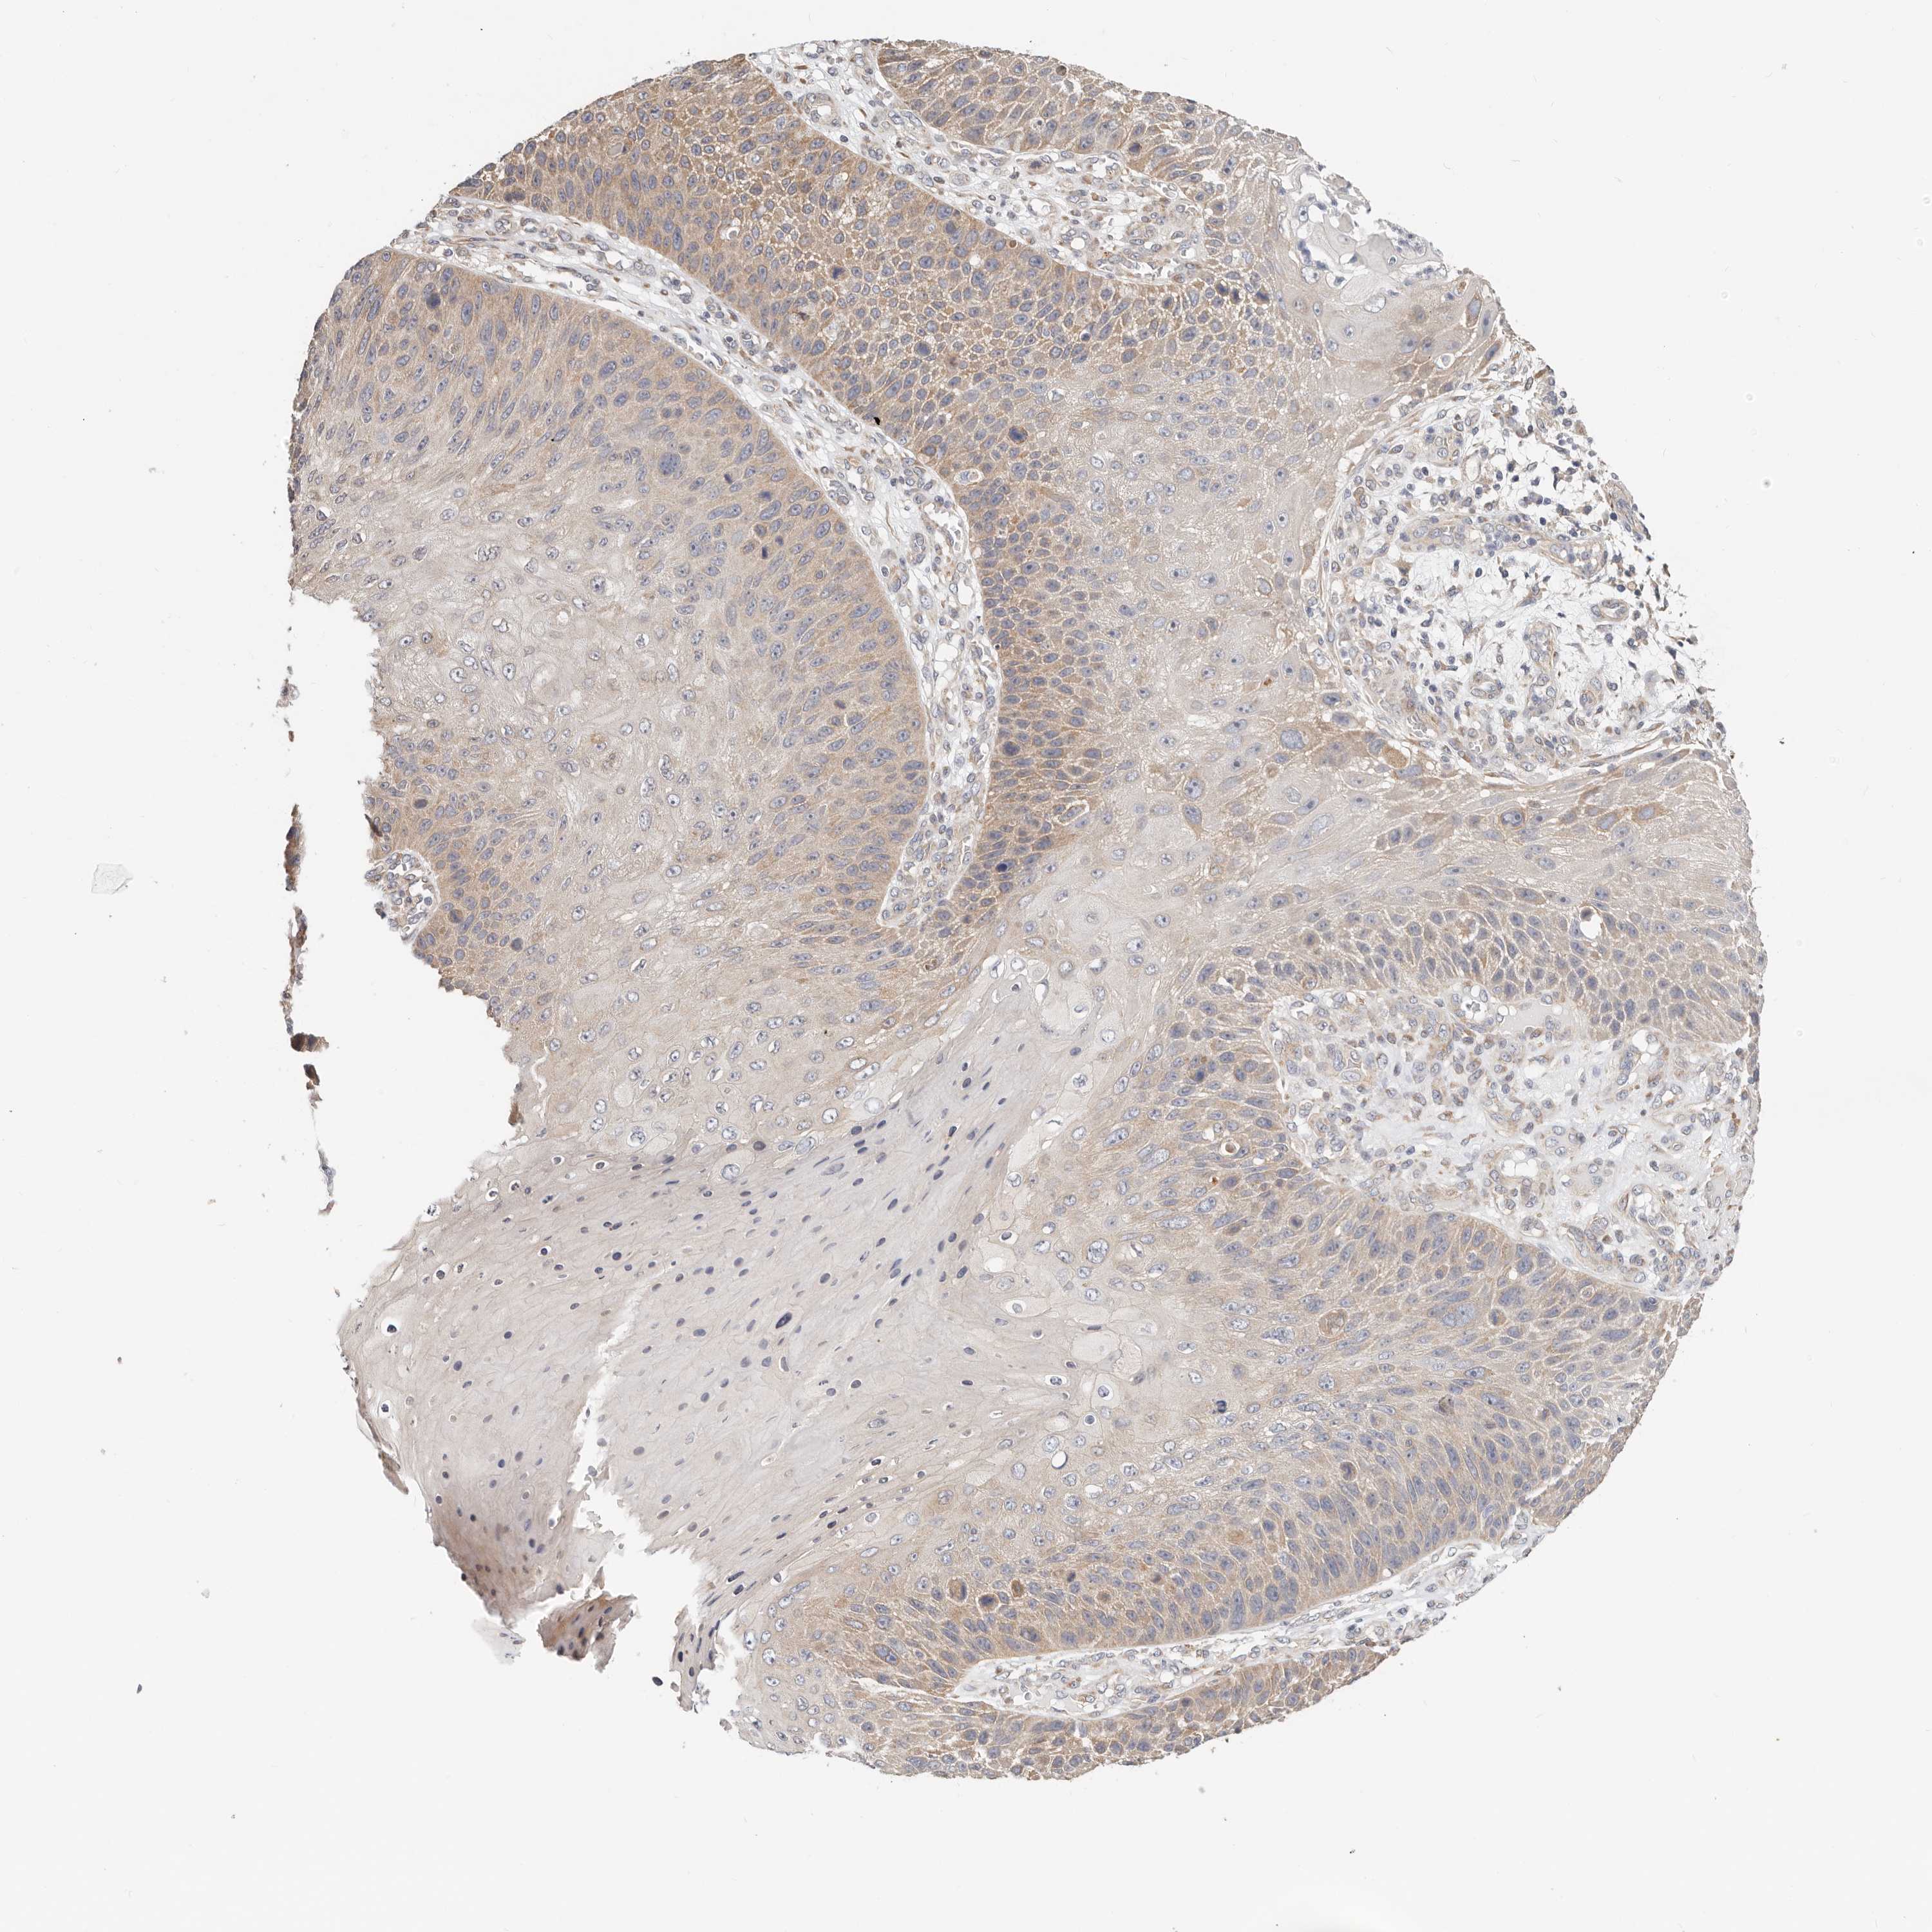

SKIN CANCER - Protein expressioni

A mouse-over function shows sample information and annotation data. Click on an image to view it in a full screen mode. Samples can be filtered based on level of antibody staining by selecting one or several of the following categories: high, medium, low and not detected. The assay and annotation is described here.

Antibody stainingi

Antibody staining in the annotated cell types in the current human tissue is reported as not detected, low, medium, or high, based on conventional immunohistochemistry profiling in selected tissues. This score is based on the combination of the staining intensity and fraction of stained cells.

Each image is clickable and will lead to virtual microscopy that enables deeper exploration of all samples and also displays staining intensity scores, fraction scores and subcellular localization as well as patient and tissue information for each sample.

HPA030212

HPA030213

HPA030214

HPA030215

CAB013496

Basal cell carcinoma

Squamous cell carcinoma, NOS

Squamous cell carcinoma, metastatic, NOS

Adnexal tumor, benign